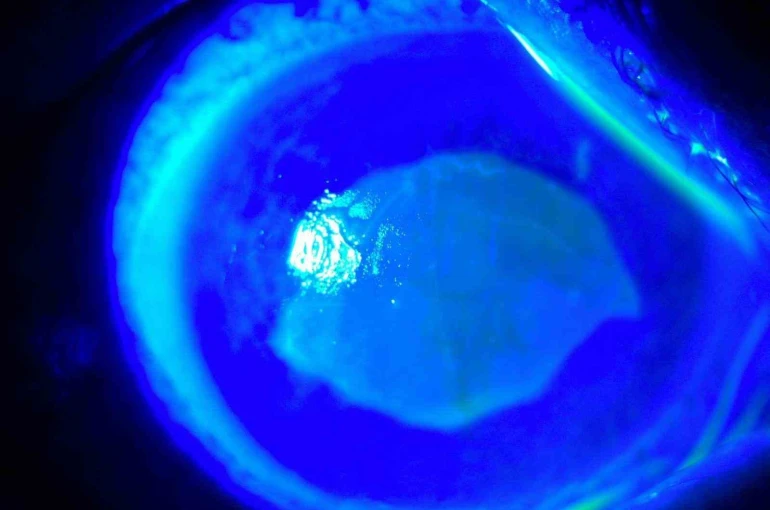

Kocaeli’nde yaşayan 52 yaşında kadın, iddiaya göre uzağı görememesi sebebiyle kullandığı gözlükten kurtulmak için yaklaşık 7 ay önce kırlangıç otunun suyunu gözlerine damlattı ve bir anda göremez hale geldi. Önce gözlerinde yanma, batma hisseden ve sonrasında açamaz hale gelen kadın hemen hastaneye koştu. O dönem Kocaeli’nde çalışan Göz Hastalıkları Uzmanı Doç. Dr. Ömer Faruk Yılmaz ve ekibi hastaya müdahale ederken korneanın en dış katmanı olarak ifade edilen kornea epitelinin zarar gördüğü belirlendi. Göze yabancı cisim, kimyasal madde kaçması ya da enfeksiyon durumlarında gözü temizlemek amacıyla uygulanan göz yıkama tedavisi gerçekleştirildi. Yaklaşık 2 haftalık tedavinin ardından hasta sağlığına kavuştu. Doç. Dr. Yılmaz, hastasının yaşadığı süreç ve tedavisine ilişkin bilgi verdi. Yılmaz, hekim önerisi olmadan herhangi bir ürün kullanılmaması gerektiğine dikkat çekerek önemli uyarılarda bulundu. Öte yandan hastanın göz bebeğinin beyazlığı ve göz akının ise kızardığı hali fotoğraf karesine yansıdı.

"Kırlangıç otu kullandı, hastamız göremez hale geldi eğer tedavi edilmeseydi sonucun ne olacağını bilemiyoruz fakat tedavi sonucunda hastamız iyileşti. Gözlerinin fotoğrafını çektirdim, kırlangıç otunun geçişini gösterdik. Tedavi edilmediği zaman göz içinde belki de körlüğe ulaşabilecek şekilde istenmeyen yan etkilere yol açabilir. Yüzlerce farklı ot olabilir, yanlışlıkla faydalı bir ot damlatacağız diye zararlı bir otu damlatabiliriz. Göze direkt damlatılması steril değildir, göze zarar verebilir, enfeksiyon oluşturabilir. Faydalı bile olsa Sağlık Bakanlığı ruhsat vermeden, ilaç formatına dönüştürmeden, uygun dozajlar ayarlanmadan ve göz hekiminin önerisi olmadan göze herhangi bir bitkisel ilaç damlatılmasını önermiyoruz."